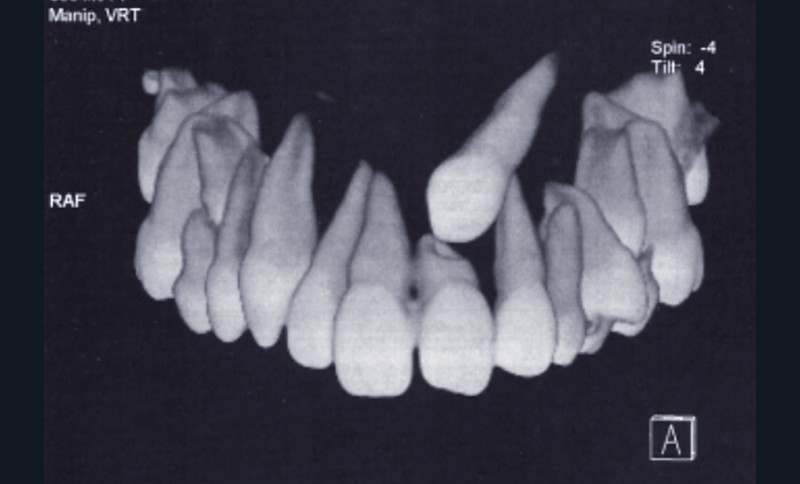

Rappel de la problématique. Mademoiselle O. âgée de 13 ans en classe I squelettique mésodivergente présente la persistance de 63. La panoramique et l’examen tomodensitométrique montrent une transposition de la 23 qui évolue au-dessus de la 21 et a entraîné une résorption radiculaire de celle-ci.

D’après les documents fournis, il s’agit d’une transposition de 23, transposition partielle, l’apex étant en bonne position (fig. 1).

La couronne de 23 est haute et discrètement vestibulaire par rapport à la racine de 21, partiellement résorbée.